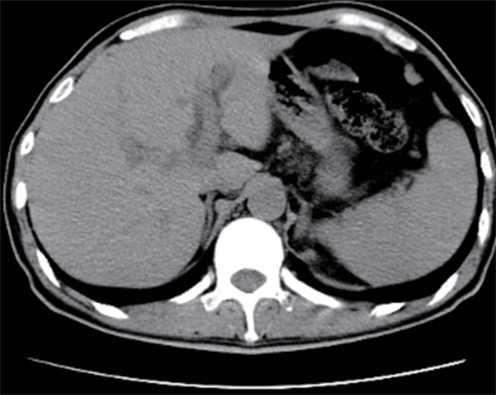

• Duodenum-preserving pancreatic head resection, also known as Beger surgery, has a high incidence rate of bile duct injury after surgery, while the treatment modality for bile duct injury depends on the severity of the injury, and endoscopic therapy is often challenging in case of severe bile duct injury. Recently a patient with biliary fistula after Beger surgery was admitted to Affiliated Hangzhou First People’s Hospital, Westlake University, and successful diagnosis and treatment were achieved through oral choledochoscopy-assisted percutaneous-endoscopic rendezvous technique.